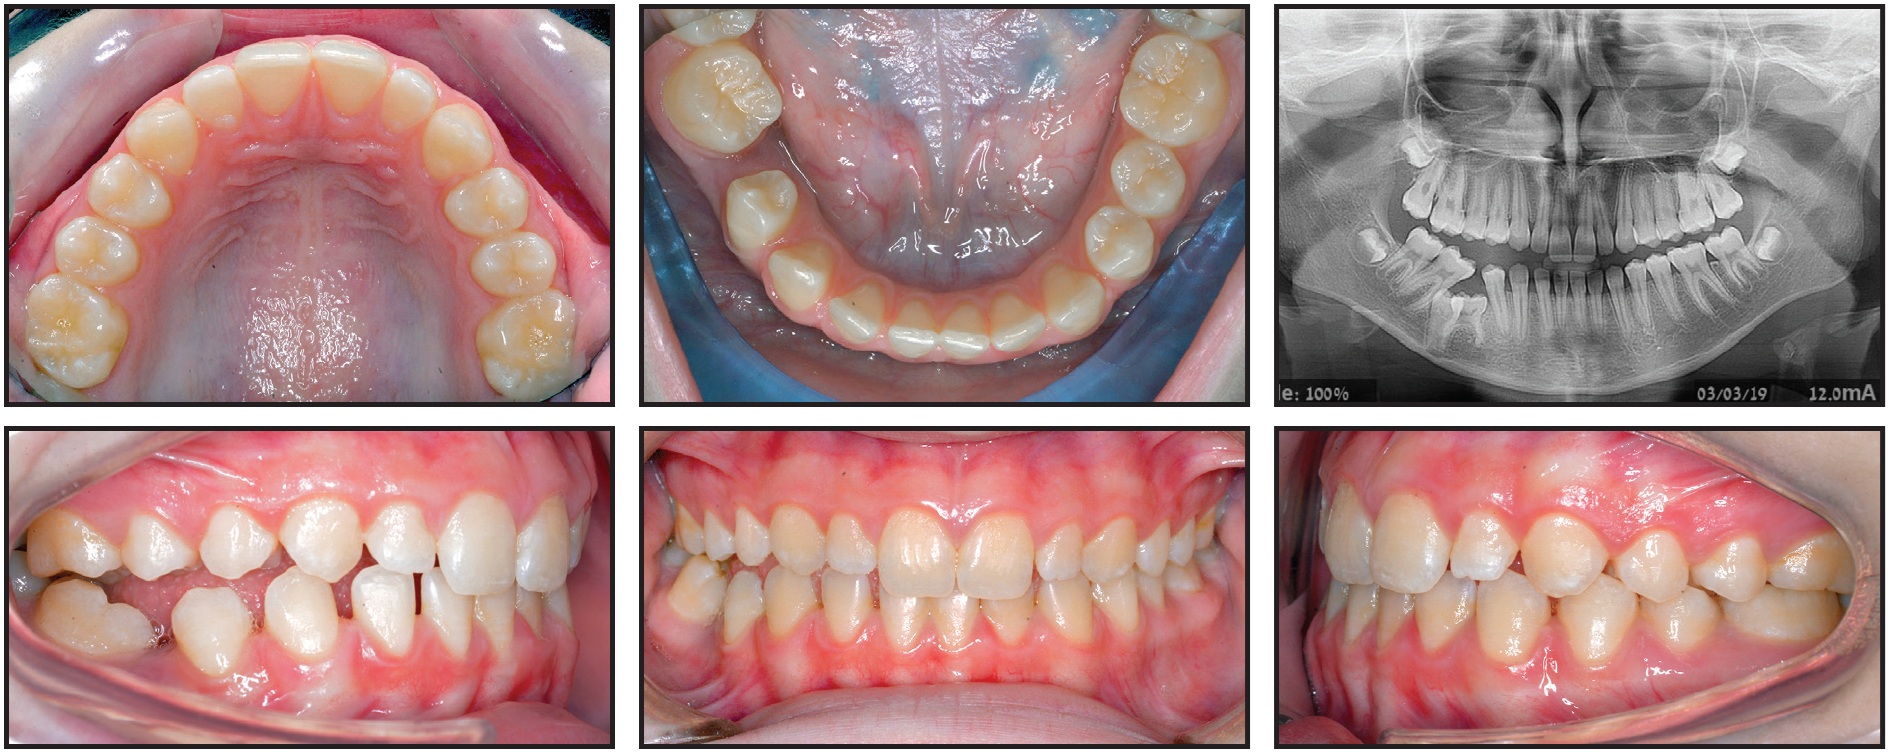

A 12-year-old female presented with a submerged lower right second deciduous molar and an impacted permanent lower right second premolar (Fig. 4A).

Fig. 4 Case 2. 12-year-old female patient with Class I skeletal pattern, impacted permanent lower right second premolar, and posterior open bite on right side due to submergence and probable ankylosis of lower right second deciduous molar. Note position of lower right second deciduous molar and lower right second premolar in relation to inferior alveolar nerve and lower border of mandible (continued in next image).

She was referred by a general dentist after complaining of pain in the lower right region, but she had no prior medical history. Clinical evaluation found a Class I skeletal pattern, a dental deviation of the lower midline to the right, and a posterior open bite on the right due to submergence and probable ankylosis of the lower right second deciduous molar. Neither the second decidous molar nor the lower right second premolar was visible clinically.

Radiographic examination revealed the positions of the submerged deciduous molar and the impacted permanent premolar, indicating their proximity to the inferior alveolar nerve canal and the lower border of the mandible, as well as the second premolar’s position relative to the adjacent first molar. A CBCT was requested for further investigation of this anatomical proximity and for surgical access planning (Fig. 4B.

Fig. 4 (cont.) Case 2. 12-year-old female patient with Class I skeletal pattern, impacted permanent lower right second premolar, and posterior open bite on right side due to submergence and probable ankylosis of lower right second deciduous molar. Note position of lower right second deciduous molar and lower right second premolar in relation to inferior alveolar nerve and lower border of mandible.